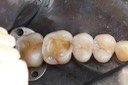

Alan Chinn #19 pre-op